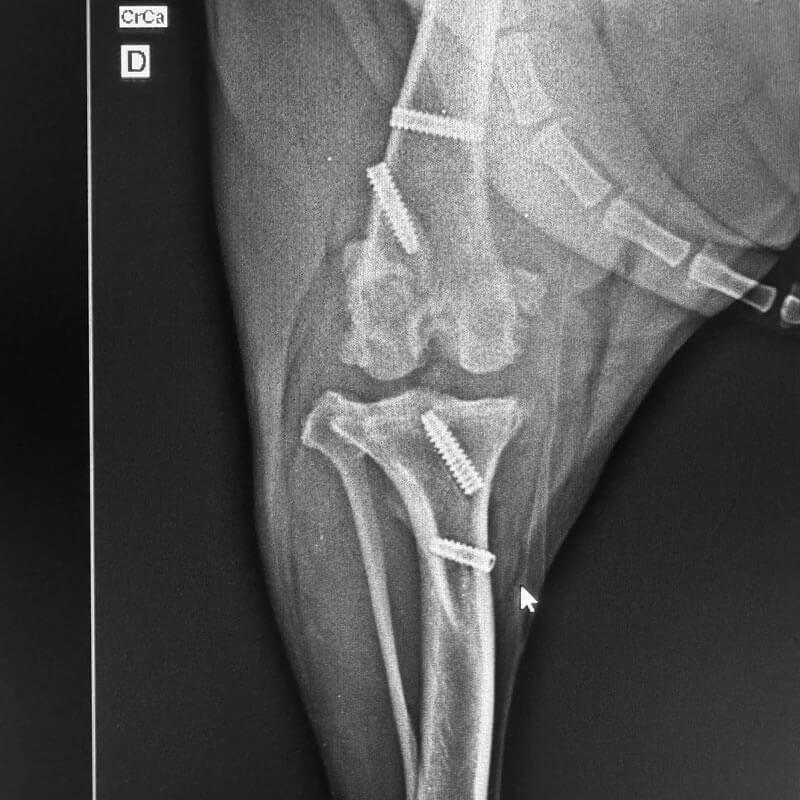

Fraturas em Ossos e Coluna

Fraturas em ossos longos e na coluna vertebral

Ruptura de Ligamento Cruzado

Doença degenerativa do joelho de caes que pode ser incapacitante se nao tratada logo.

Traumatologia

Atendimento emergencial para fraturas e traumas, com estabilizações e reconstruções ósseas.